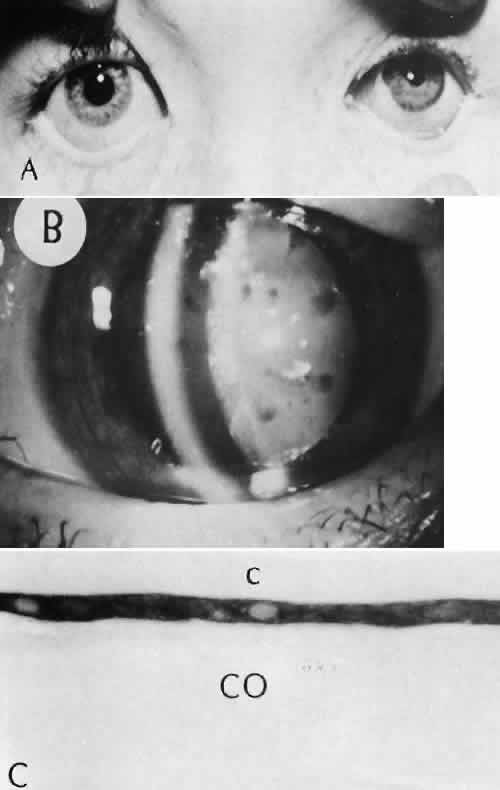

Descemet's membrane is only loosely adherent to the posterior stroma and may be stripped into the anterior chamber at the time of the corneal incision placement (Fig. 27) or injection of sodium hyaluronate. Splitting off of Descemet's membrane from the posterior cornea can lead to postoperative intractable corneal edema.89,90

Fig. 27. A case of stripping of Desce-met's membrane during a filteringprocedure (scleral cautery and iridectomy). A. The clinical appearance was one of extensive filtering bleb formation superiorly and regional dense corneal edema and opacification. B. The anterior chamber remains formed. Detached Descemet's membrane can be seen protruding into the anterior chamber. The patient died shortly after surgery from unrelated causes.C. The gross appearance of the area of detached Descemet's membrane extending into the anterior chamber.D. On the histologic section, the origin of detached Descemet's membraneextends to the region of the limbal wound. (Hematoxylin-eosin stain; × 16.) (Kozart DM, Eagle RC Jr: Stripping of Descemet's membrane after glaucoma surgery. Ophthalmic Surg 12:420–423, 1981.)